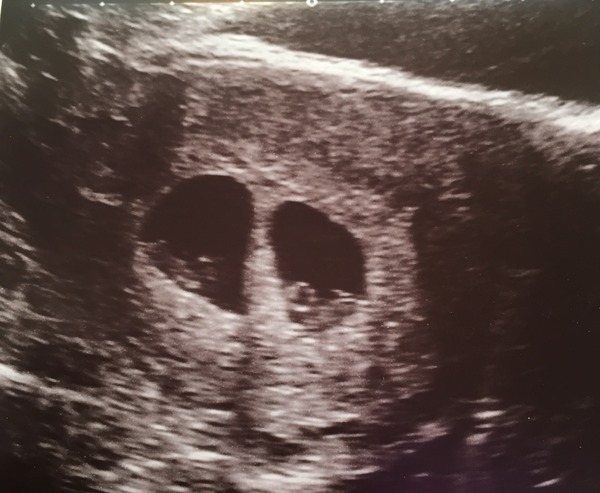

I had spotting over the weekend. Really panicked. Managed to get a scan this morning. TWO heartbeats!!! I am expecting twins! Measuring 6+4 and 6+6!!